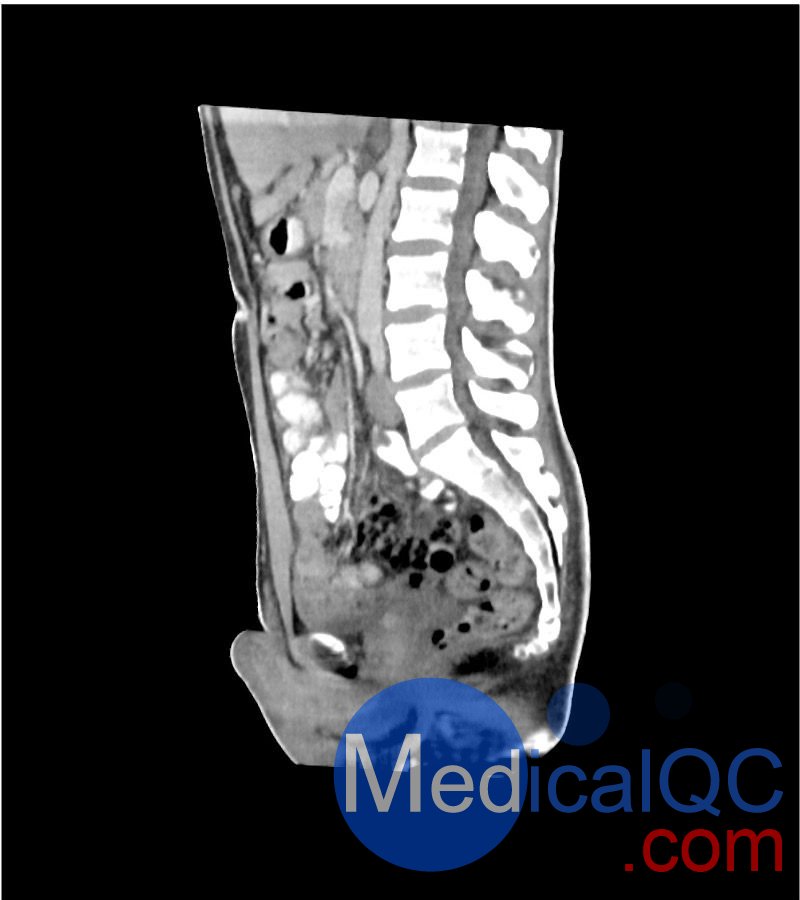

WEK-5501男性腹部模體,WEK-5501男性骨盤模體可模擬門靜脈期的腹部和盆腔增強掃描效果,掃描范圍覆蓋第一腰椎至?xí)巺^(qū)域。

該體模右側(cè)設(shè)有髂淋巴結(jié)腫塊(模擬病灶)。

1. 可對脈管系統(tǒng)、骨骼及軟組織進行逼真模擬,涵蓋的器官包括肝臟、膽囊、胰腺、脾臟、腎上腺、腎臟、胃、小腸、結(jié)腸、膀胱及前列腺。

2. 右側(cè)設(shè)有髂外淋巴結(jié)腫塊(模擬病灶)。

WEK-5501男性腹部模體,WEK-5501男性骨盤模體成像效果圖: